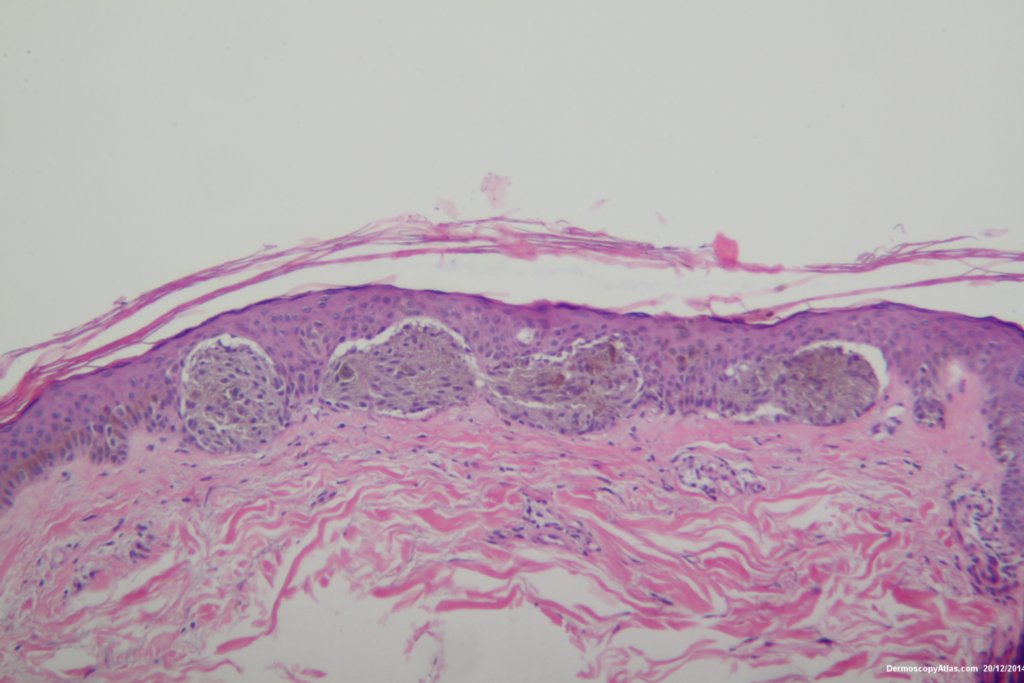

The histopathology shows nests of epitheliod and spindled cells with lots of melanin in them. There are a few melanophages in the dermis. There is no inflammatory reaction beneath this lesion. There were no mitoses. This is just a junctional lesion ie no nests of cells in the dermis.